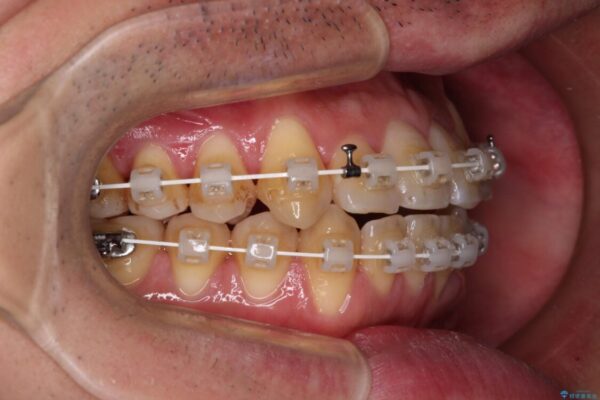

マウスピース矯正での自己管理には自信がないとのことで、ワイヤー装置による矯正治療を行うこととしました。

クロスバイトは、治療の過程で咬み合わせが大きく変化する期間があり、食事が取りにくくなってしまいます。

また、装置が対合歯と咬み合ってしまい、頻繁に脱落するなど、色々と面倒なことがあり、治療がスムーズに進まないことがあります。

治療途中

• 八重歯とクロスバイト 目立たないワイヤー装置で矯正治療 治療途中画像